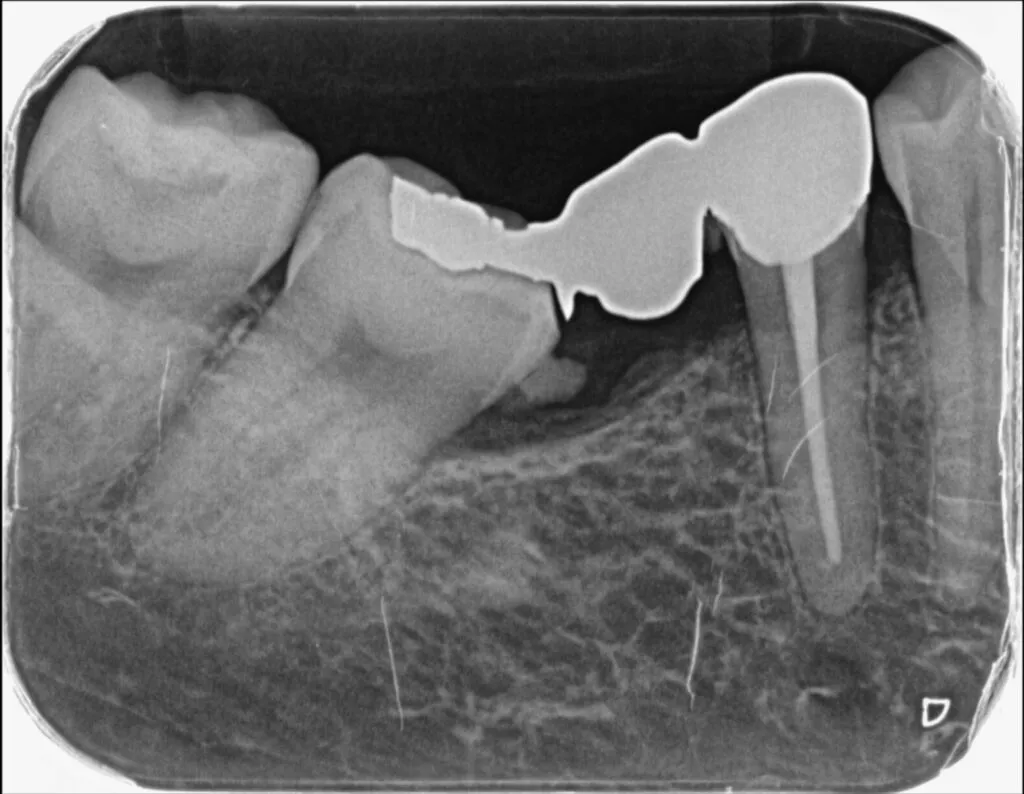

隙間があいている前歯を移動させる場合や、傾いている歯をまっすぐに修正する場合に有効な治療法です。またむし歯が骨の中まで進行した場合、通常は歯を抜くことになりますが、歯を引っ張りあげることで、保存できる場合もあります。